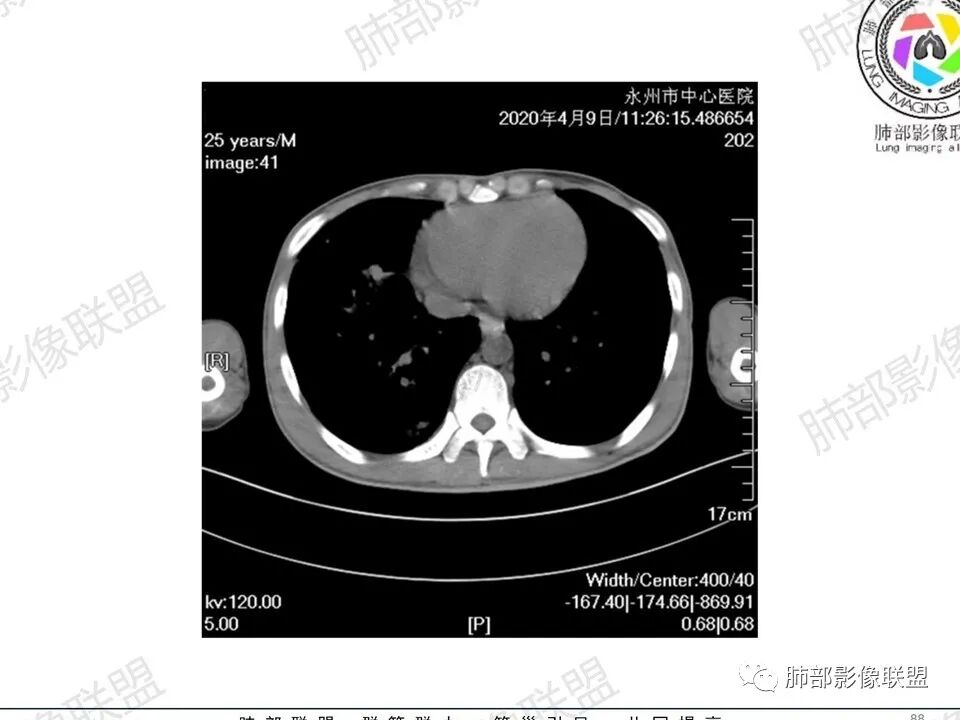

3、影像表现:双肺散在斑片影及结节影,部分结节内可见血管穿行,斑片影沿支气管血管束分布,近胸膜侧病变收缩不明显。部分中央淋巴间质增厚,小叶间隔增厚。病灶内支气管穿行,部分支气管略扩张。局部小结节呈串珠样改变。纵隔、肺门区、锁骨上及腋窝淋淋巴结肿大,部分有融合。心腔低密度。脾大。

5.双肺门及纵隔淋巴结显著增大,这改变相当显眼。这里强调“双肺门”及“多发”!

增大的淋巴结密度偏低且均匀。此外患者有体表淋巴结增大。

1.临床表现明显,纵隔及双肺门淋巴结显著肿大,临床最为担心的还是淋巴瘤!

尤其患者有贫血及脾脏增大,又有体表淋巴结增大时,这也是临床相对常见的情形。

淋巴瘤肺部浸润表现多样,多发结节影是其最常出现的影像学改变,尤其是霍奇金病。

2.右肺多发微小结节影,部分沿血管束分布,尽管未见小叶间隔改变,但双肺门淋巴结增大确实应当首先排除结节病,但经验上说,结节病的增大淋巴结密度往往较高、较密实,边界往往清楚,“独立性”很强,绝无“融合之嫌”!此外,较少出现贫血、脾大,临床表现也往往较轻微。